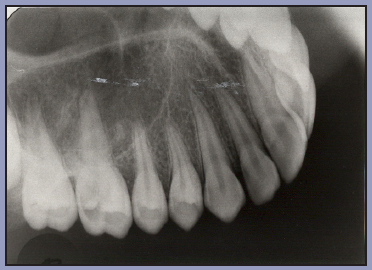

Bitewing examinations were introduced by Dr. Raper in 1925. Bitewing images focus on the clinical crowns of both the maxillary and mandibular teeth. Bitewings do not show the apices of the tooth and cannot be used to diagnose in this area. The greatest value of bitewing radiographic images is the detection of interproximal caries in the early stages of development, before it is clinically apparent. The arrows in Figure 2 indicate areas of interproximal caries. Bitewing images also reveal the size of the pulp chamber and the relative extent to which proximal caries have penetrated.

Figure 2 – Bitewing Images

Figure 2